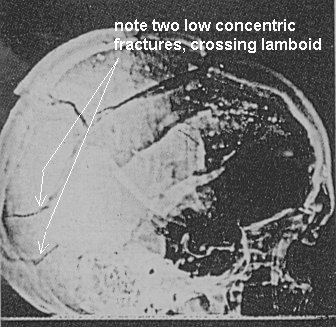

Sicherlich zieht man AUCH zum Festellen der Verletzungen die Röntgenbilder hinnzu. Aber du wirst es wieder als "entweder-oder" auffassen. Knochenbeschädigungen fallen natürlich bei Röntgenbildern sofort auf.

Commander HUMES - The X-rays made of the wound in the head of the late President showed fragmentations of the missile. Some fragments we recovered and turned over, as has been previously noted. Also we have X-rays of the fragment of skull which was in the region of our opinion exit wound showing metallic fragments.

http://mcadams.posc.mu.edu/russ/testimony/humes.htm (Archiv-Version vom 11.03.2016)Man erkennt sogar Fracture lines, die vom "occiput" ausgehen. Und da dieselben Pathologen auch den autopsiebericht geschrieben haben, in dem die "fractures" erwähnt werden, haben sie sich die Röntgenaufnahmen unter diesem Aspekt auch angeschaut

There was a shelf and then a little hole came up on the side and then one of the smaller of the two fragments in that X-ray, when that arrived, we were able to fit that down there and complete the circumference of that bone wound.